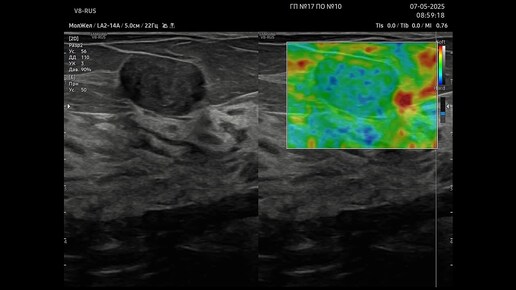

Ультразвуковая диагностика (УЗИ). Доктор Иогансен. Видеопримеры. Выпуск 123. Фиброаденома молочной железы (5).